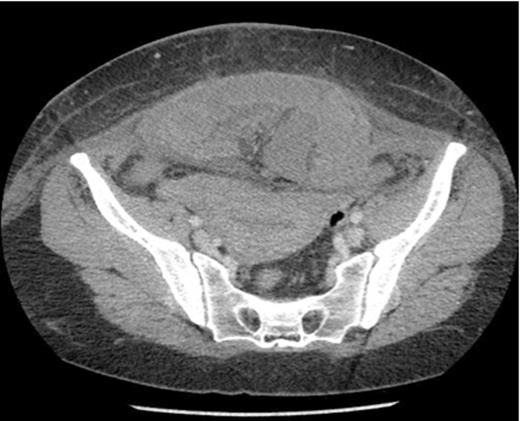

Sagittal section showing dilated loops of small bowel and a segment of small bowel adherent to the anterior abdominal wall.

The next day she became pyrexial (38°C) and tachycardic (103 bpm). Examination revealed a tender abdomen, with guarding and absent bowel sounds. Her neutrophilic leukcytosis increased from 13 to 27 and CRP increased to 159. She was commenced on gentamicin and a CT abdomen/pelvis was ordered. Radiology reported a high-grade acute SBO secondary to herniation of segment of small bowel into anterior abdominal wall defect. A laparotomy was performed and revealed a segment of strangulated small bowel lying above the rectus muscles and trapped beneath the intact rectus sheath. 34cm of necrotic small bowel was resected and an end to end anastomosis was fashioned. The patient made a good post-operative recovery and was discharged 9 days later.